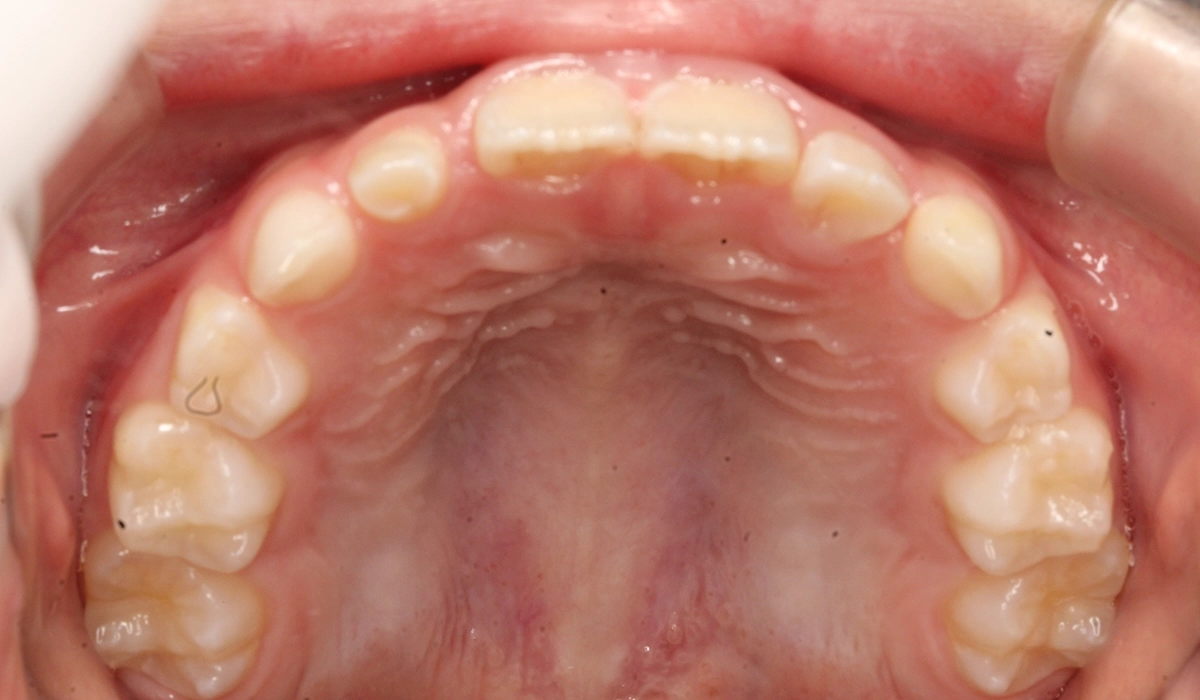

術前:下顎

術後:下顎